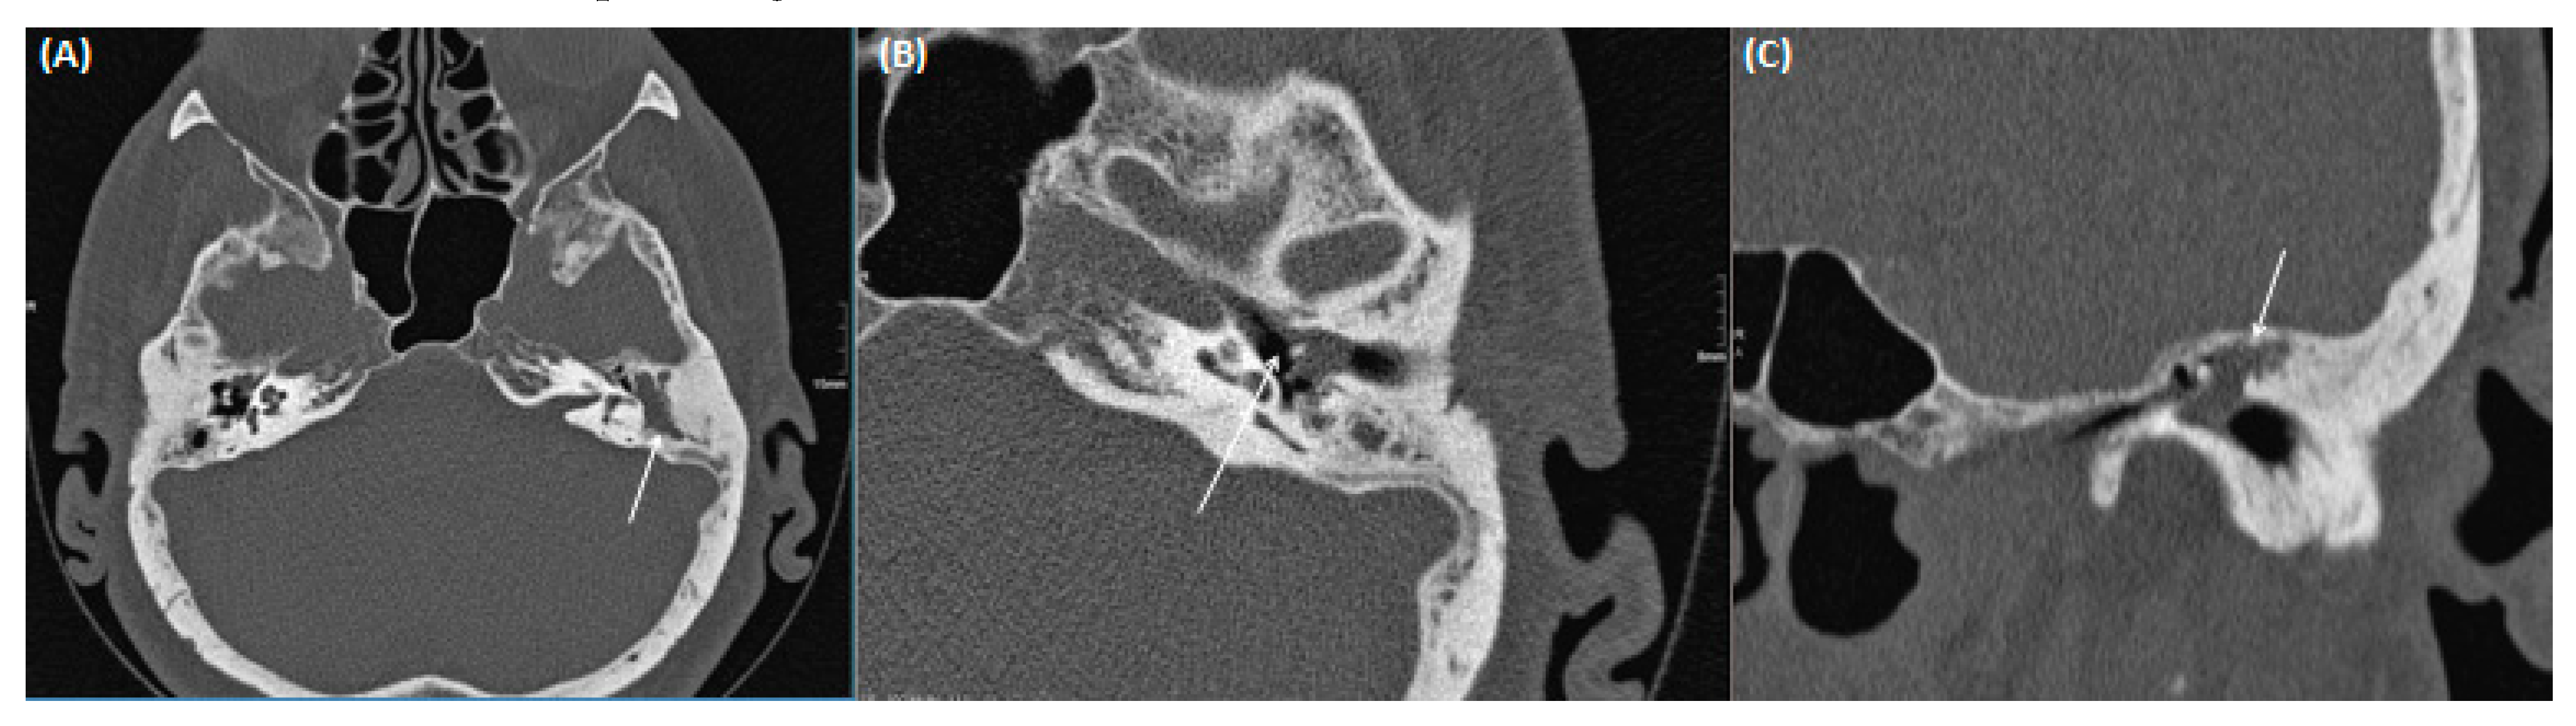

3.2.1. Acute/Chronic Otitis Media

3.2.2. (Oto-)Mastoiditis

3.2.3. Tympanosclerosis

3.2.4. Cholesteatoma of the Middle Ear